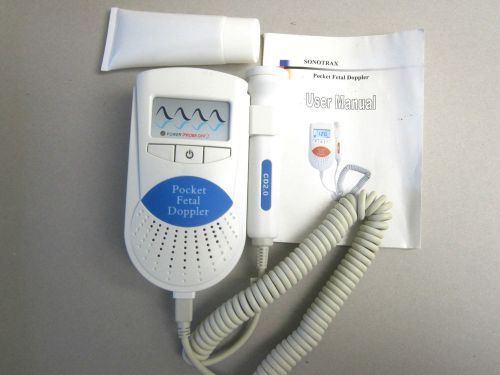

Ultrasound Pocket Fetal Doppler Heart Rate Monitor (Sonotrax-A)